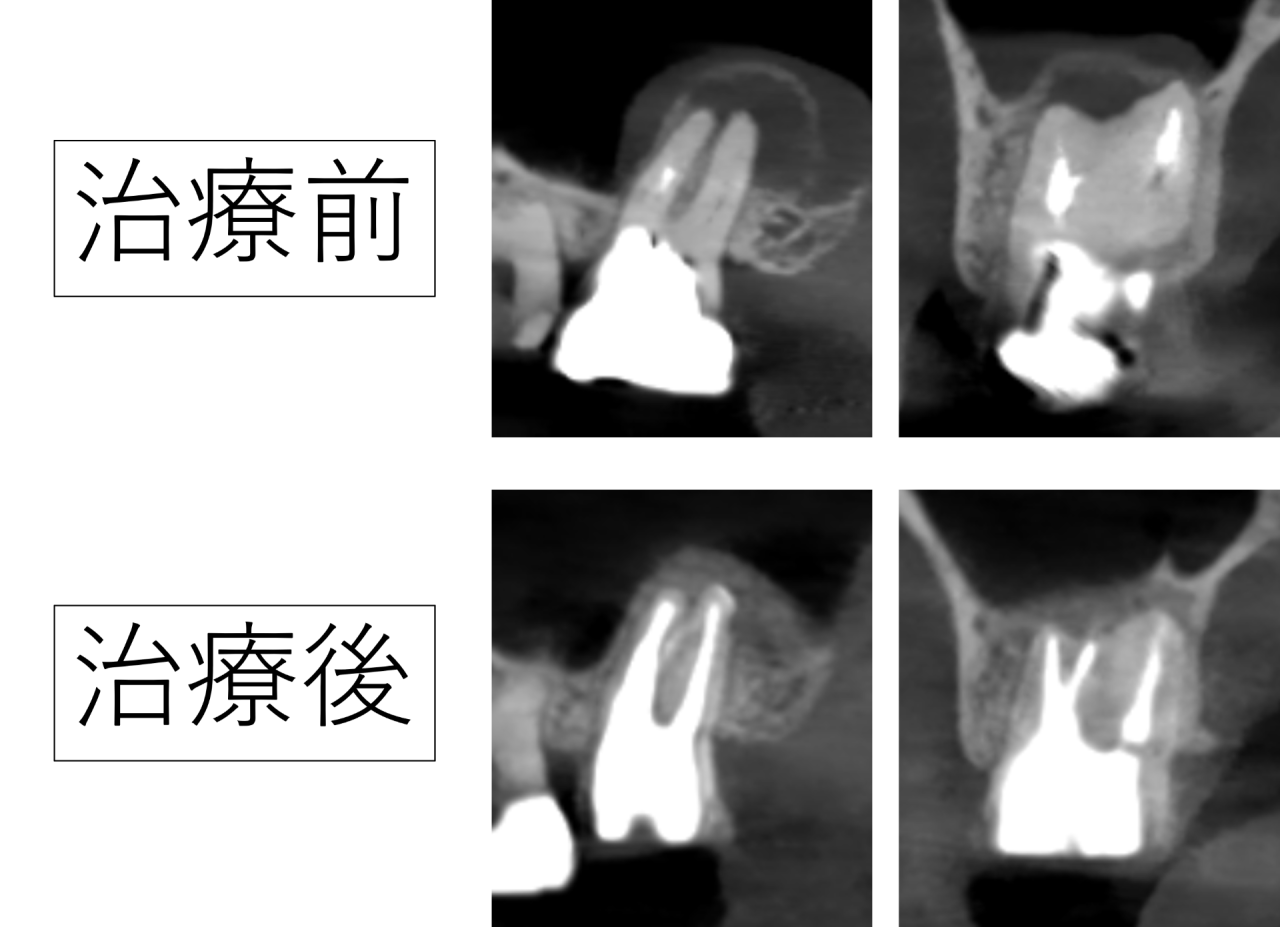

検査で見つかった根の先の大きな病変

今回の症例は右上奥歯でした。レントゲン撮影を行うと、根の先に大きな黒い影が確認されました。これは根の先で炎症が続き、周囲の骨が吸収されている状態を示しています。鼻の領域である上顎洞にも炎症が波及しそうで、じきに蓄膿などの症状も出るかもしれません。

患者さんは過去に神経を取る治療を受けていました。神経を除去した歯は痛みを感じないと思われがちですが、実際には内部に感染源が残っている場合、根の先で炎症が持続することがあります。

炎症が慢性的に存在していると、普段は違和感が軽くても、体調が悪い時や疲労が強い時に痛みが強くなります。今回のケースも、まさにそのような経過でした。

1年後に確認できた骨の回復(再生)

治療から1年後にレントゲンで経過を確認したところ、以前は大きく写っていた病巣(骨の吸収像)が縮小し、周囲の骨の回復(再生)が確認できました。1年での回復とても早いです。患者様はとても喜ばれました。